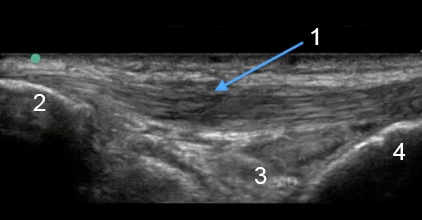

Thickened Patellar Tendon

Patella

Hoffa Fat Pad

Tibia